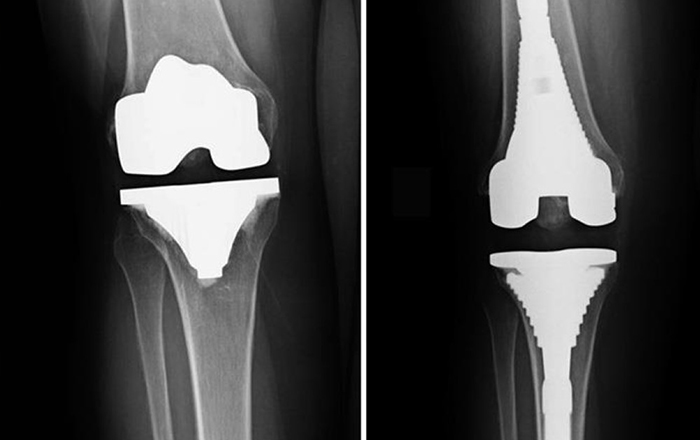

Diz Protezi (Total Diz Artroplastisi)

Diz protezi, diz eklemi yüzeylerinin hasar ettiği durumlarda uygulanan cerrahi tedavidir:

Preoperatif Dönem

• Detaylı klinik değerlendirme

• Radyolojik incelemeler (Radyografi, BT)